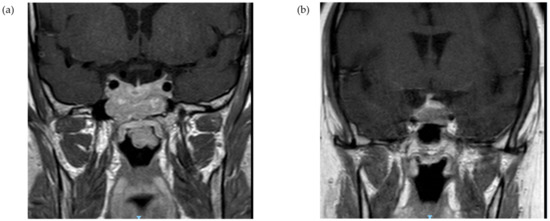

Figure 3.

Illustrative radiographic MR imaging. Coronal T1, non-contrast (a) suprasellar and infrasellar lesion with a large exophytic portion invading into the nasopharynx, involving the clivus and the sphenoidal sinus (Patient #6); (b) a suprasellar lesion invading into the left cavernous sinus (Patient #12).

Among patients with corticotroph macroadenoma, data on the radiographic characteristics were available for 23 out of 25 tumors. Suprasellar extension was reported for 15 patients (65.2%) with optic chiasm compression in six cases (26.1%). Cavernous sinus invasion was evident in 10 cases (43.5%), and sphenoid sinus invasion was documented for five patients (21.7%) (illustrative MR imaging, Figure 3). From a clinical standpoint, six patients (26.1%) reported headaches, and five patients (20.0%) had visual complaints, including two patients with bitemporal hemianopsia (Table 3). Median UFC values were highest for tumors with sphenoid sinus invasion (median, 5.8 × ULN; IQR, 3.1–23.5 × ULN) or cavernous sinus invasion (median, 5.8 × ULN; IQR, 3.2–11.6 × ULN), followed by tumors with suprasellar extension with no cavernous sinus invasion (median, 4.4 × ULN; IQR, 2.3–11.0 × ULN) or intrasellar macroadenomas (median, 4.6 × ULN; IQR, 3.6–8.8 × ULN) (p = 0.67). Urinary free cortisol levels >4 × ULN were reported for four out of five patients (80%) with sphenoid sinus invasion and for six out of ten patients (60%) with cavernous sinus invasion, compared with four out of eight (50%) patients with suprasellar extension with no cavernous sinus invasion and two out of four patients (50%) with intrasellar tumors. Similarly, serum cortisol levels following low-dose DST were higher among patients with tumors invading the sphenoid sinus (reported in two patients: 513 and 1004 nmol/L) or the cavernous sinus (reported in three patients: 410, 509, and 1004 nmol/L), compared with intrasellar tumors (median, 324 nmol/L; IQR, 93–984 nmol/L) (p = 0.57). Furthermore, median ACTH concentrations were highest for patients with sphenoid sinus invasion (median, 2.0 × ULN; IQR, 1.2–3.1 × ULN), or cavernous sinus invasion (median, 2.0 × ULN; IQR, 1.0–2.3 × ULN), followed by the suprasellar extension (median, 1.7 × ULN; IQR, 0.9–2.3 × ULN), and lowest for those with intrasellar macroadenomas (median, 0.5 × ULN; IQR, 0.3–1.9 × ULN) (p = 0.32).